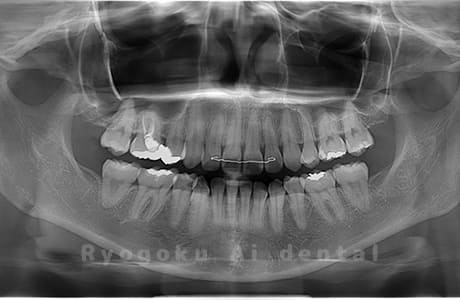

真っ直ぐ生えている親知らず

親知らずが真っ直ぐ生えているタイプです。

このタイプは真っ直ぐ生えていて咬み合わせに問題がなければ、抜歯しないケースもあります。ただし、虫歯になっていたり、痛みがあったり、咬み合わせが悪かったりすると抜歯をおすすめします。